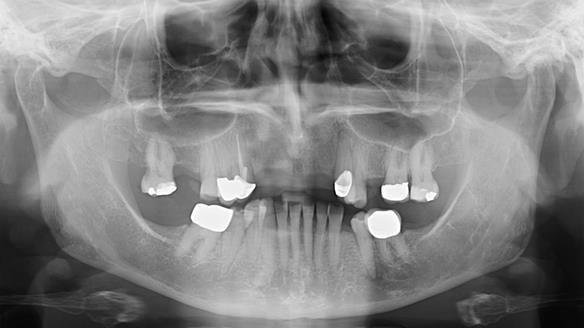

This is one of those cases that reminds me why I love removable prosthodontics. Pam was an absolute joy to treat — we were on the same page throughout. Her old upper flexible denture was loose, uncomfortable, and unaesthetic. We replaced it with a carefully designed metal-based upper partial denture/splint and new porcelain-bonded-to-zirconia (PBZ) crowns for the canines. The result is stable, comfortable, and natural-looking.

- Diagnosis and plan – Flexible upper denture ill-fitting with poor stability, retention, and appearance. Plan: metal-based upper partial denture/splint with lighter porcelain-bonded-to-zirconia crowns on UR3 and UL3.